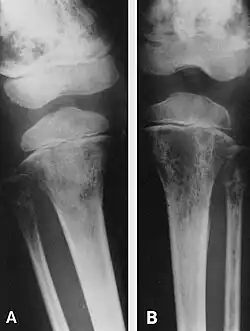

Ocenie wielkości ogniska pierwotnego i ewentualnych przerzutów służą badania obrazowe:

- rtg jamy brzusznej i klatki piersiowej

- tomografia komputerowa lub MRI okolicy guza